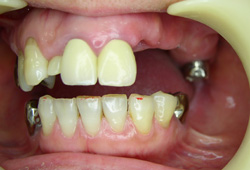

Pérdida de múltiples dientes

La pérdida de múltiples dientes es la ausencia de varios dientes que puede ser resultado de caries, enfermedades periodontales o traumatismos.

Los pacientes notan varios espacios vacíos en su boca, lo que afecta su capacidad para masticar y hablar adecuadamente.

El tratamiento incluye la colocación de varios implantes dentales para restaurar la función y la estética.